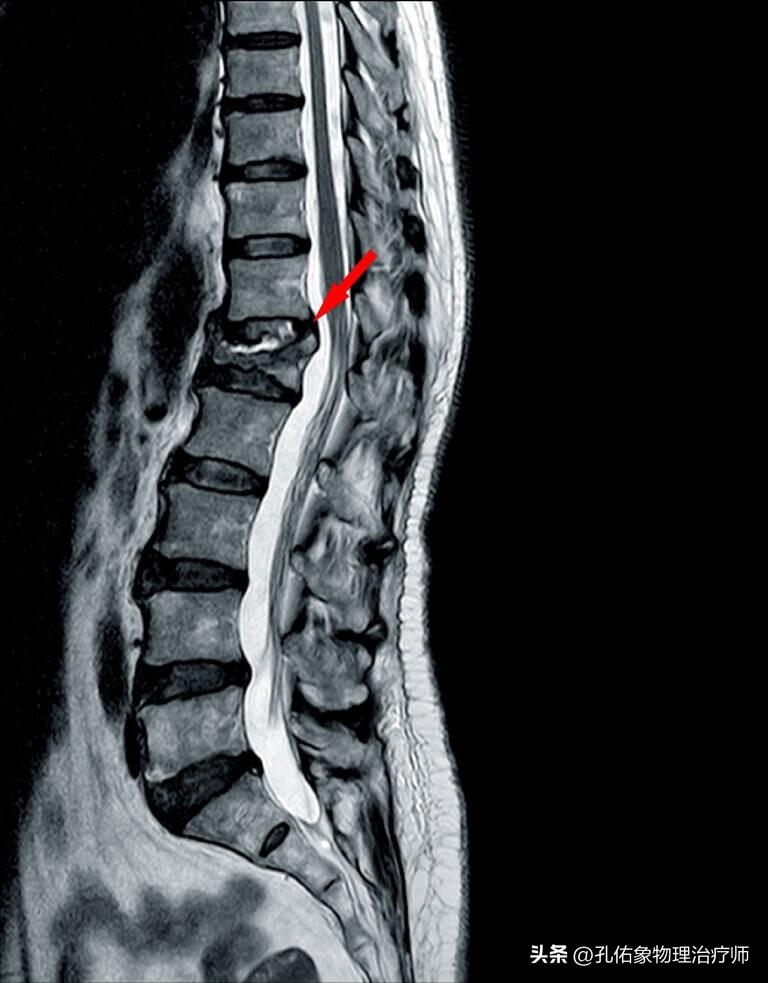

所以,经常看到高龄老年人都存在明显的驼背,这往往和骨质疏松有关系;试想我们的椎体在正常时候,类似于正方形;但随着骨质疏松加重,椎体的形状也开始了变化,从正方形变成了楔形,这在临床上就叫做“压缩性骨折”。如下图所示:

然而对于老年人骨质疏松严重,出现压缩性骨折时, 椎体成形术 可以完美解决上述问题。 这个手术就是通过注射骨水泥到骨折的椎体内,起到填充、复位压缩椎体的作用。 如下图所示: